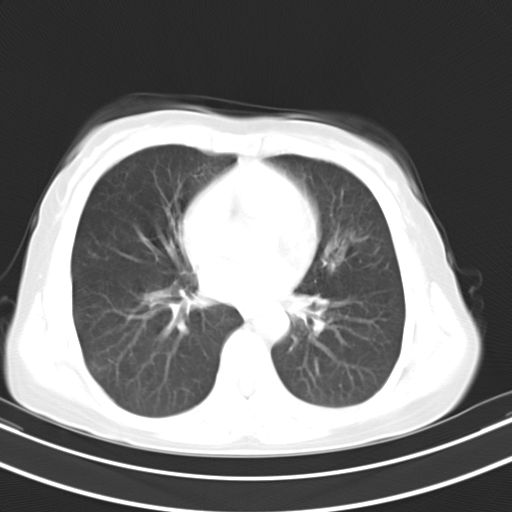

女,47岁,咳嗽胸痛一个星期,我们考虑肺结核,左下肺病灶肿瘤像不像,请高手指点。急。

考虑两肺炎症,左胸腔积液,建议治疗后复查!

考虑炎性病变,左肺舌叶病灶需要与早期肺脓肿鉴别(结合实验室),左侧少量胸腔积液。

右肺为炎性改变,左肺病灶影像所见1、楔状实变影,边缘呈刀切样,见支气管气象,2、近端纹理影增重。

并从一元化来解释,还是符合炎性病灶。建议抗炎后复查。

两肺病变考虑炎症可能性大。(左肺病变呈楔状实变影,有支气管气象,近端纹理影增重)。

1)右肺上叶前段及左肺上叶舌段感染性病变;建议抗炎治疗后复查。2)左侧少量胸腔积液。